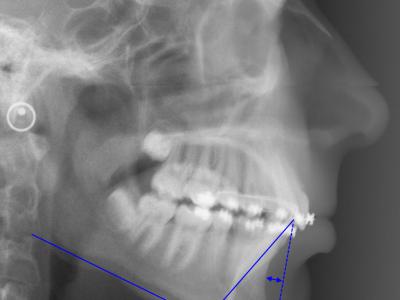

Téléradiographie de profil initiale, IMPA = 108° (a),

à 11 mois post-opératoires avec 8 mois de nivellement sur arc rond, les incisives mandibulaires se redressent spontanément de 11° (IMPA = 97°) et la concavité de la symphyse diminue significativement (b),

superposition avec le logiciel Procuste (Rouge = Avant / Bleu = Après) (c).

Téléradiographie de profil avant traitement (a),

téléradiographie de profil de réévaluation à 12 mois de traitement multi-attaches montrant l’aggravation de la proalvéolie mandibulaire avec IMPA=110° (b), l’affaiblissement labio-mentonnier est décidé à ce moment,

téléradiographie de profil en fin de traitement après 9 mois de finitions sur multi-attaches et 1 an de contention, l’IMPA est réduit à 100° et le muscle mentonnier s’est relâché (c),

superposition avec le logiciel Procuste (Rouge = Avant / Bleu = Après) montrant le redressement radiculaire des incisives mandibulaires et la croissance mandibulaire (d)